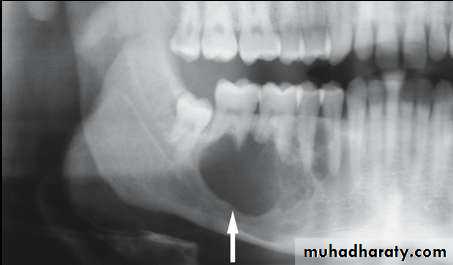

• Ameloblastoma

• Radiography:• Uni or Multilocular radiolucent areas

• Soap bubbles

• Copyright 2003, Elsevier Science (USA). All rights reserved.• Ameloblastoma

• Radiography:

• Soap bubbles appearance